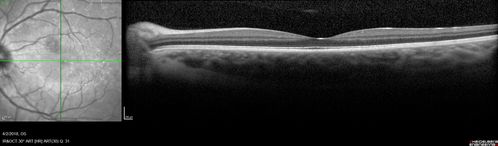

Cat Scratch - Neuroretinitis OD AND retinitis OS - Bartonella henselae positive

27 year old female with exposure to cats and prior fever.  Reports with recent vision loss right eye.  She was treated with doxycycline and within 2 weeks the right eye looks better.  Then she skipped all follow-up visits.  The right eye presented 20/200 and the left 20/16